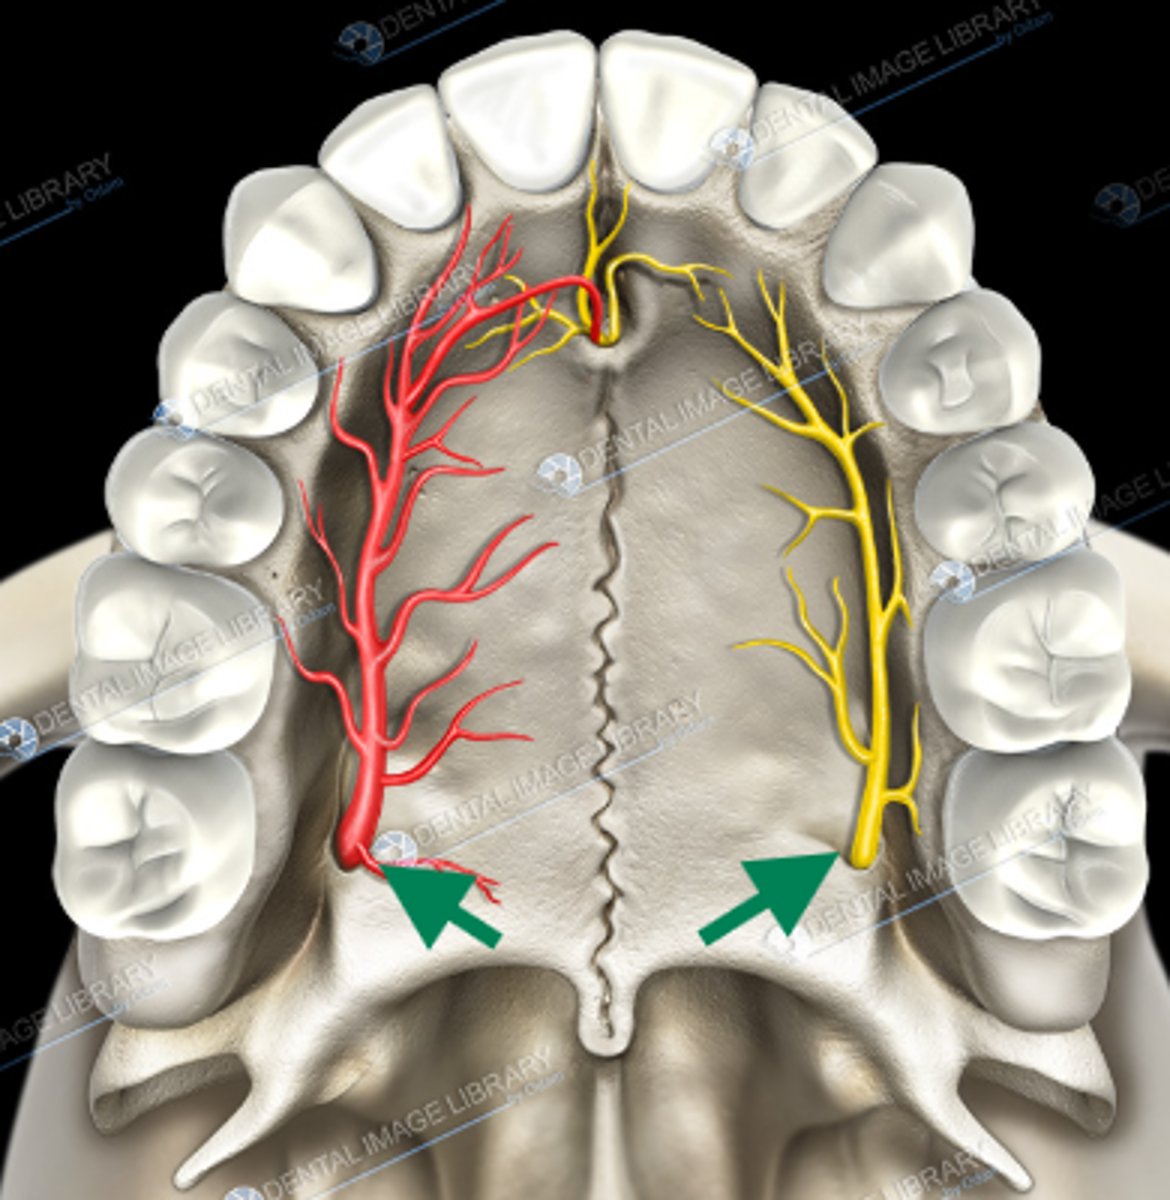

nasopalatine nerve

descending palatine artery

greater palatine nerve

greater palatine artery

greater palatine foramen

lesser palatine nerve

lesser palatine artery

greater and lesser palatine nerve

greater palatine nerve